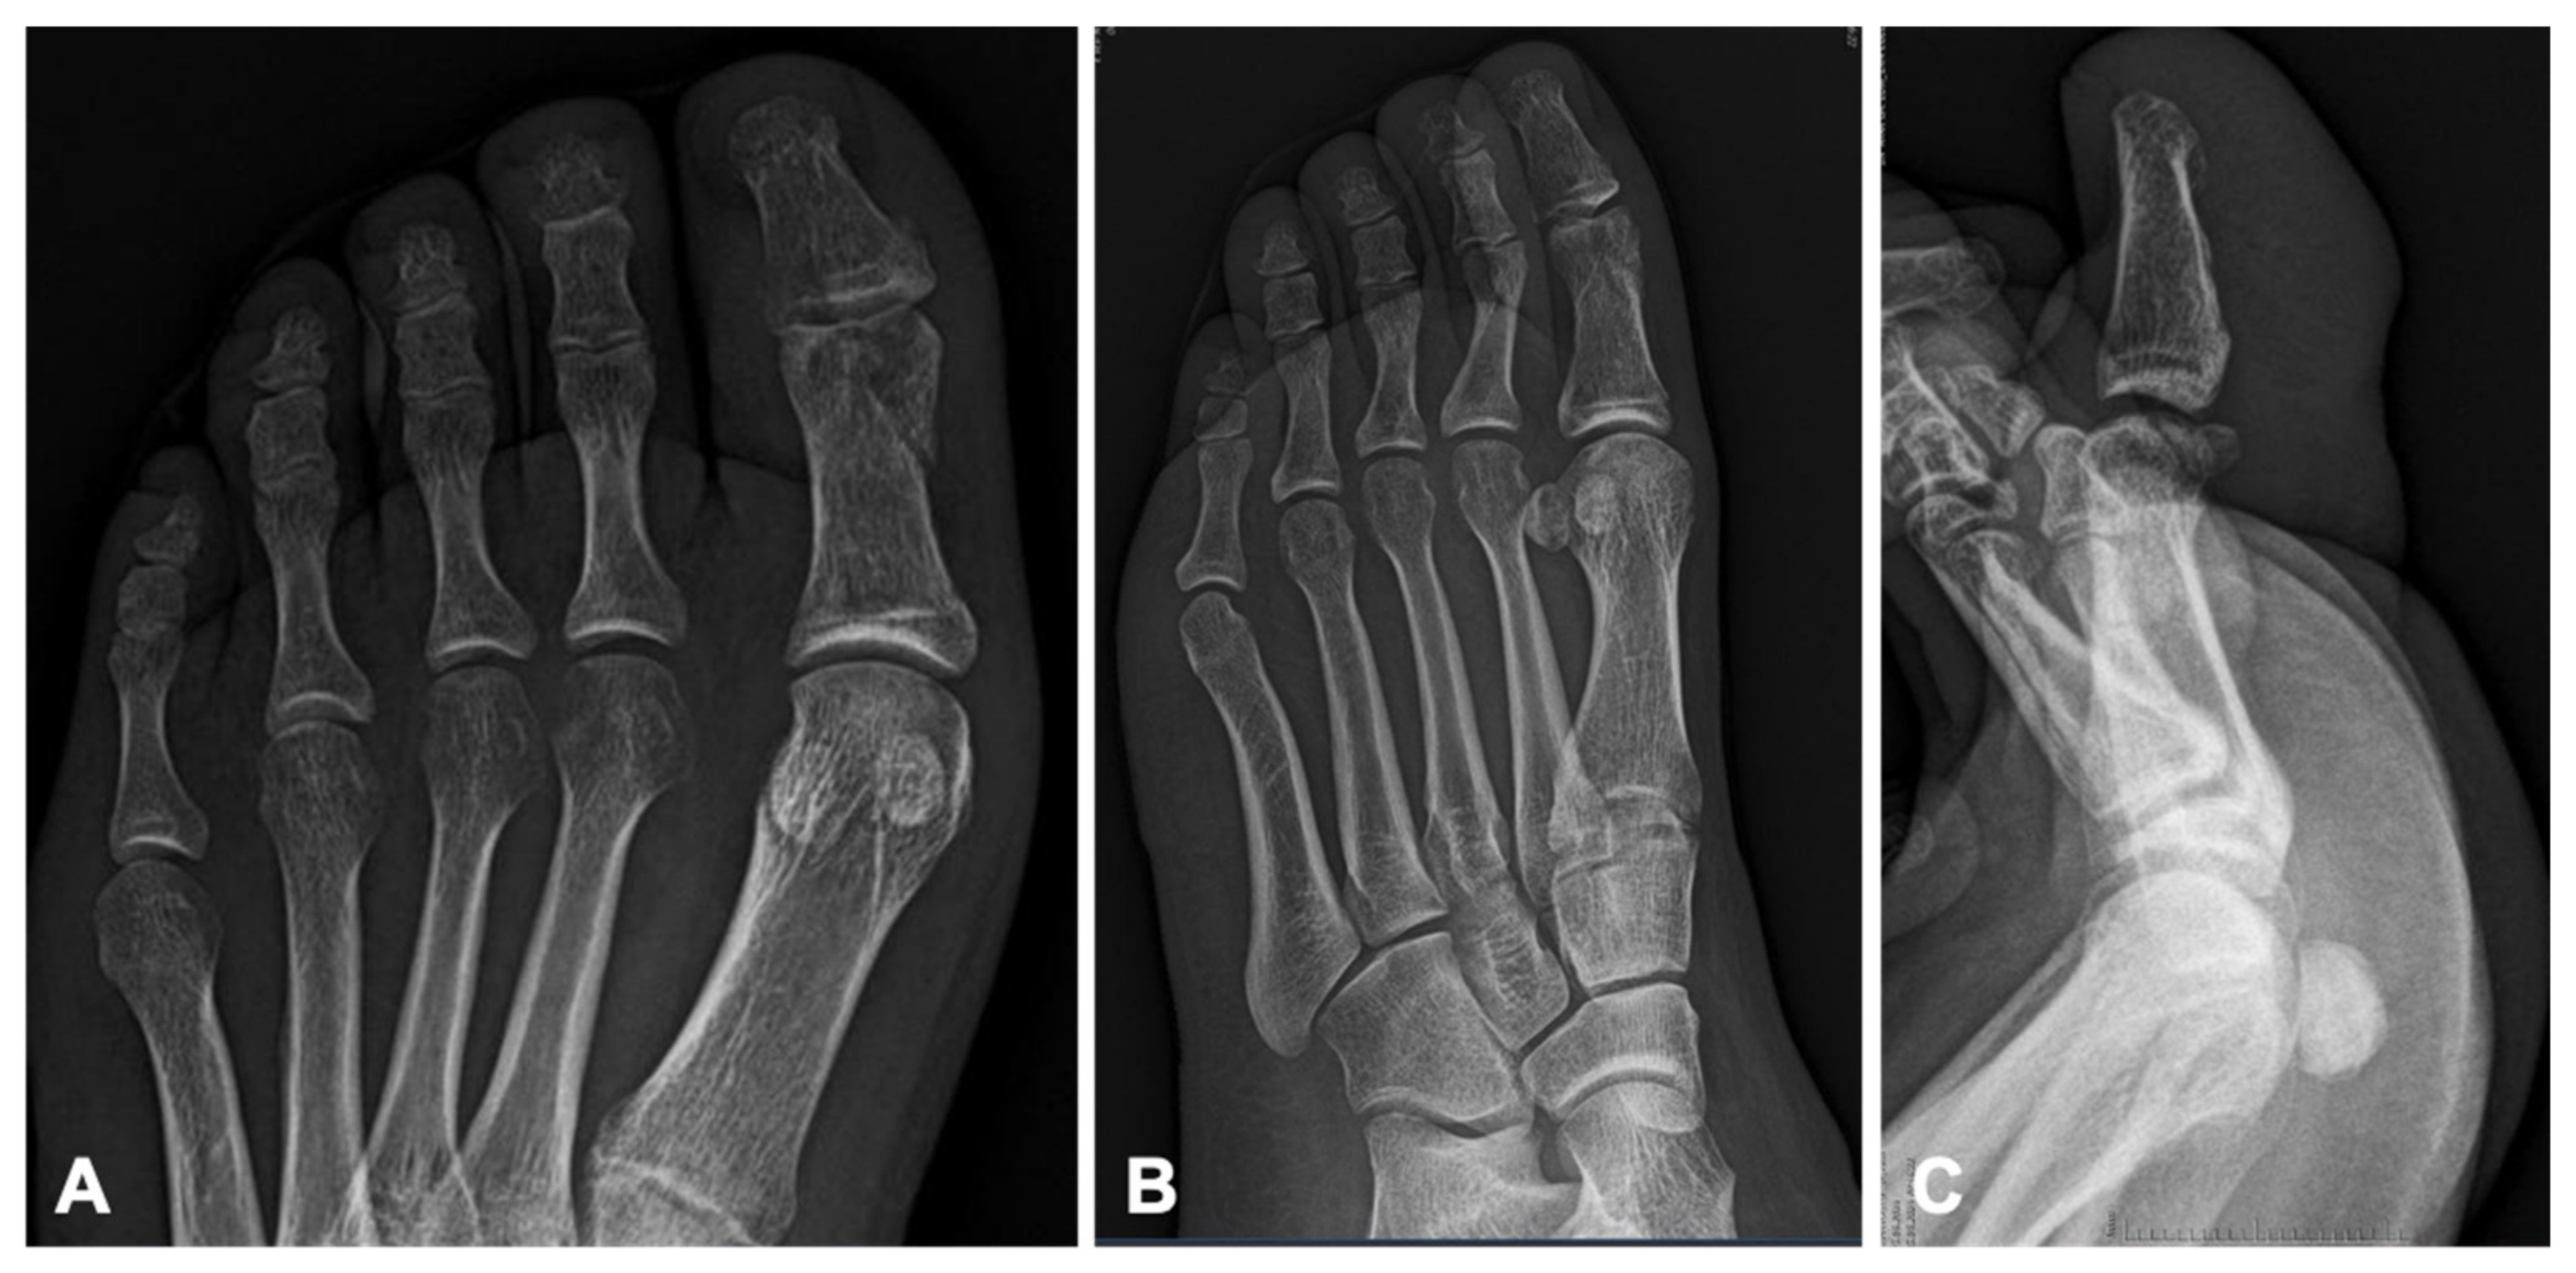

Informed consent was obtained from the patient for the publication of this case report. A 30-year-old female patient was admitted to the emergency department following a motor vehicle accident in which her left foot was trapped beneath a motorized vehicle. Clinic and radiographic evaluation revealed an open fracture of the proximal phalanx of the left hallux with 1 cm long skin cut, extending into the interphalangeal joint, accompanied by joint dislocation (

Figure 1).